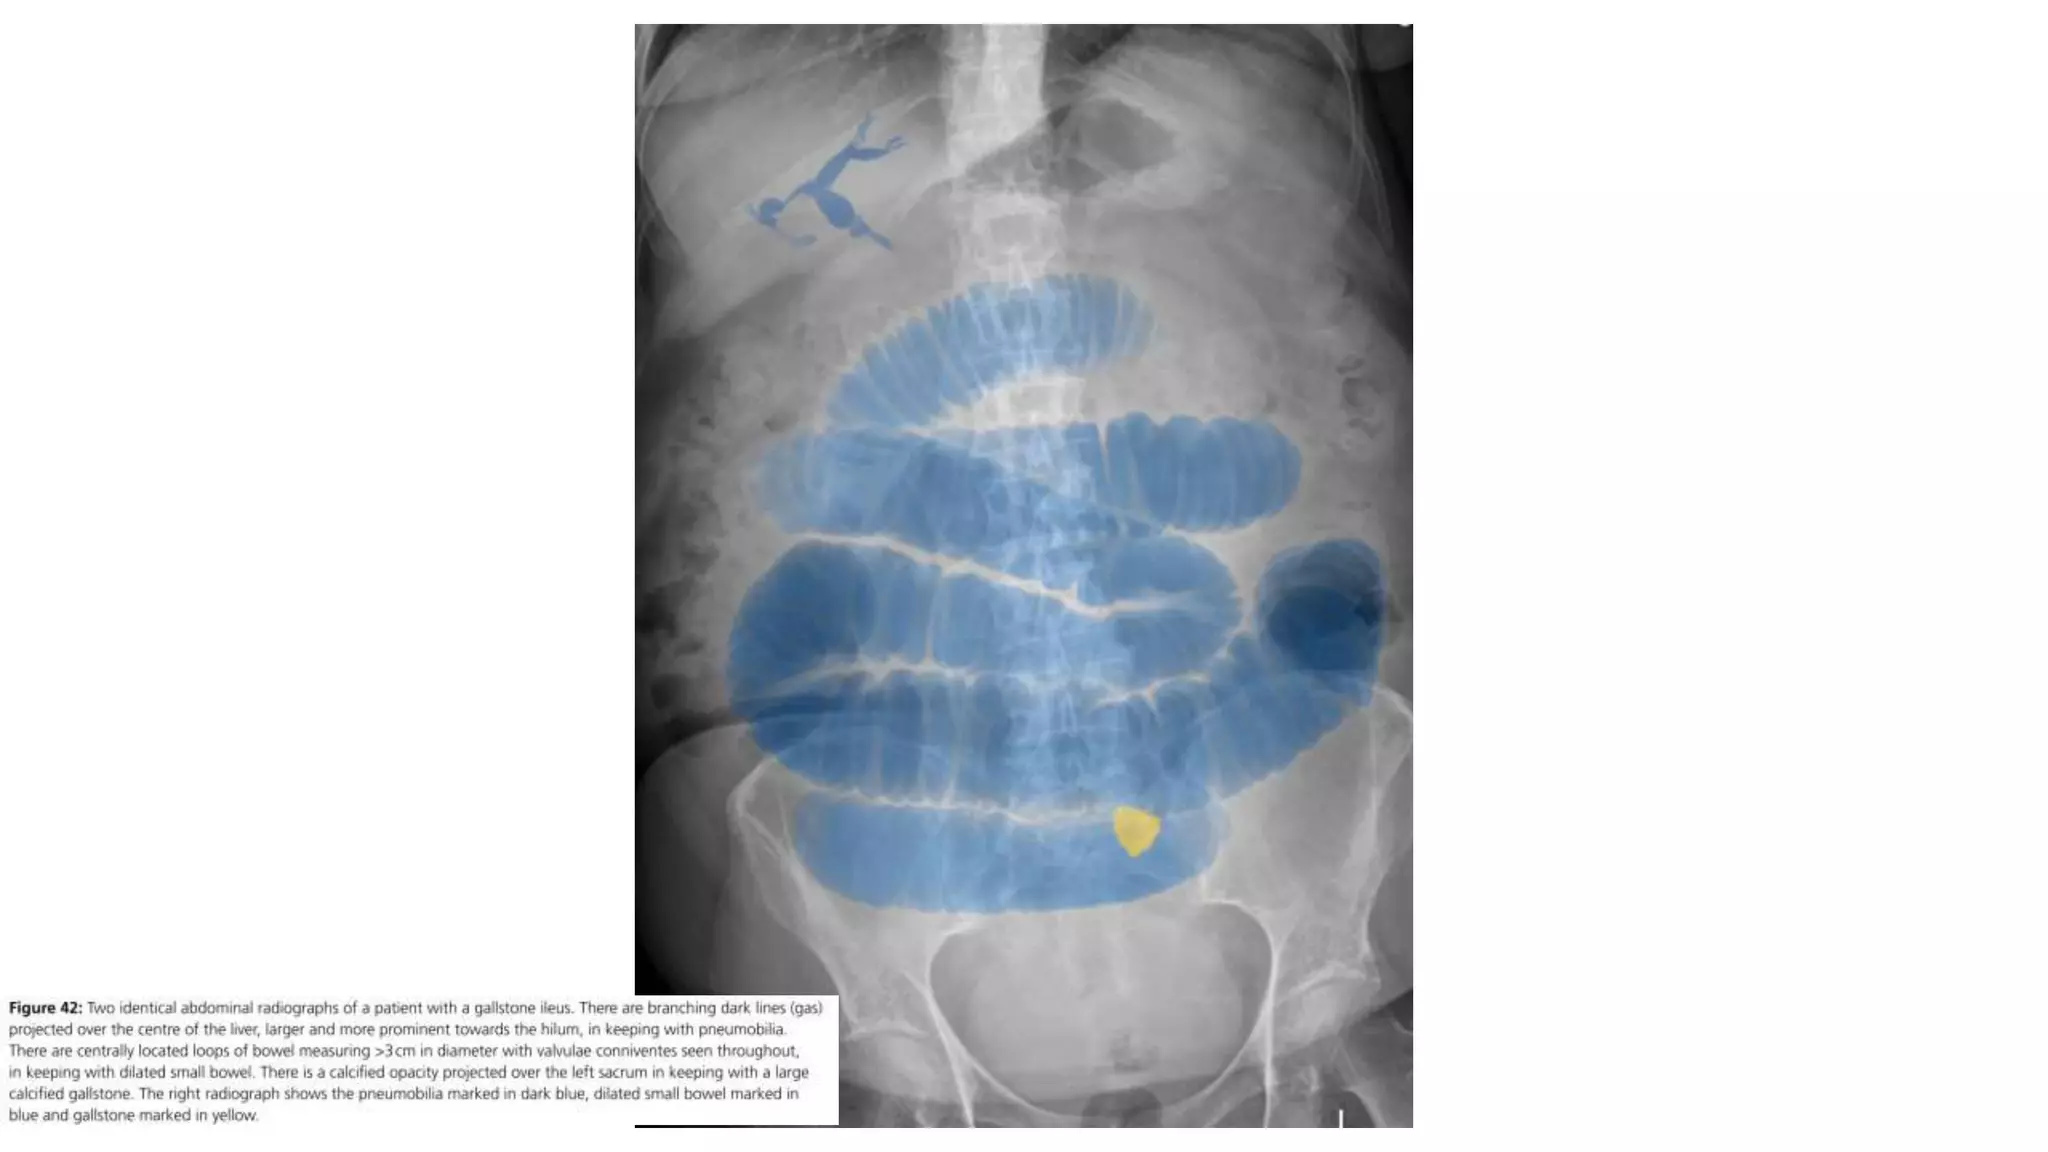

Radiological features in large bowel obstruction

• Colonic distension usually visualized in the periphery

• show the hustrations of the Taenia Coli.

• absence of rectal air and air fluid level if ileocecal valve incompetent

• May also demonstrate the cause of obstruction (volvulus)

Radiological signs to look for:

• Dilation >3 cm: The small bowel is dilated if it measures over 3 cm in

diameter.

• Central location: The dilated loops are more likely to be centrally

located on the abdominal radiograph.

• Valvulae conniventes: These are the mucosal folds of the small

intestine. They are thin, closely spaced and classically seen as a

continuous thin line across the entire width of the bowel.

• Air fluid level in upright position